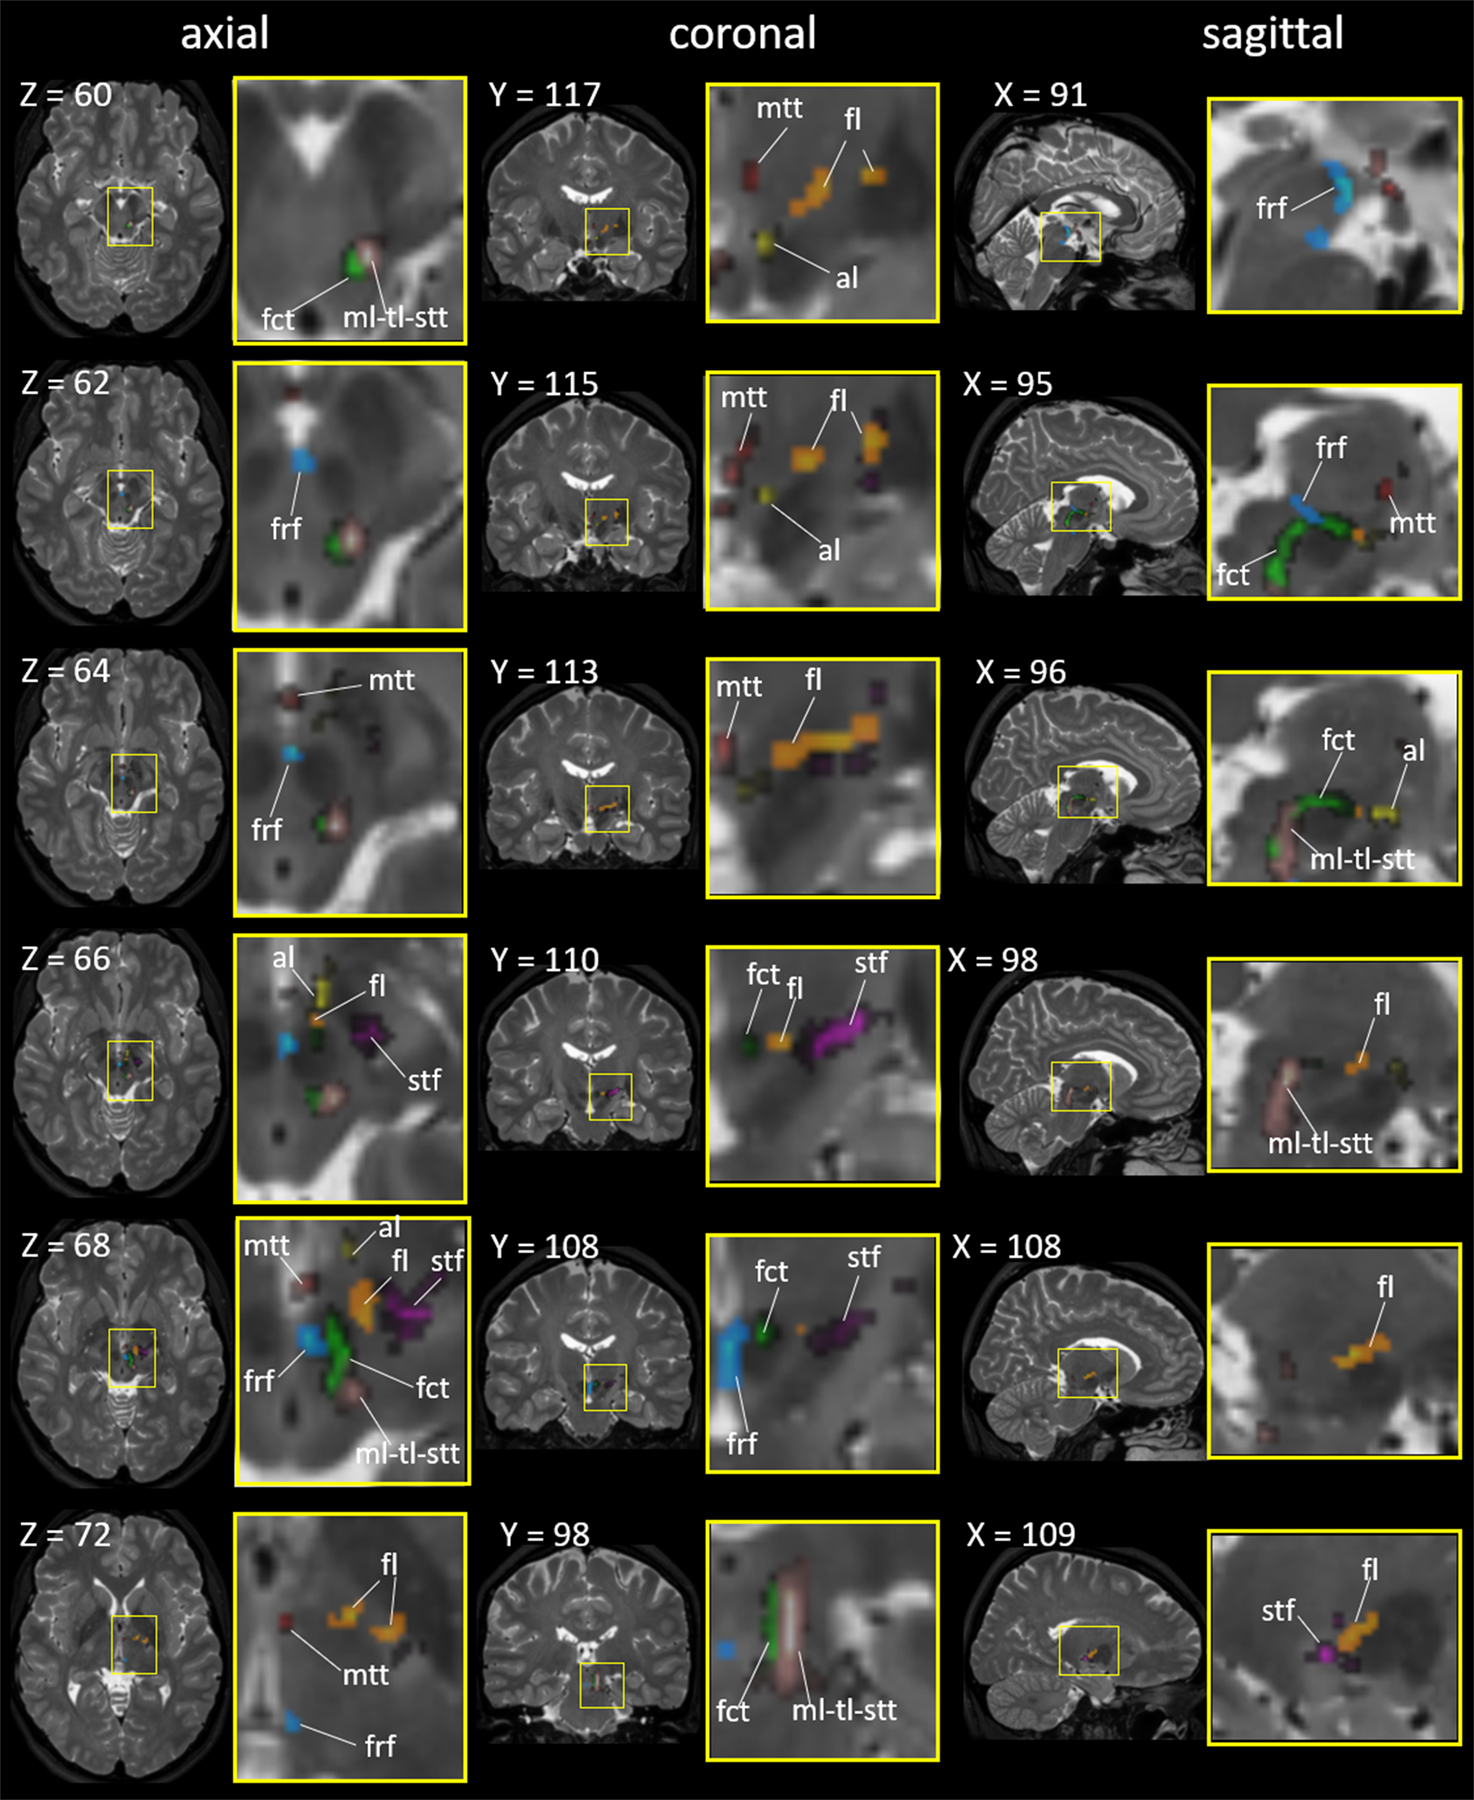

Fig. 6:

The seven fiber tracts superimposed on the in vivo T2-weighted brain MRI atlas in the Montreal Neurological Institute (MNI) coordinates. The areas surrounded by yellow rectangles (left) are magnified (right). The X, Y, and Z numbers indicate the slice numbers of the JHU-MNI atlas (Oishi et al. 2009). Abbreviations: al, ansa lenticularis (yellow); fl, lenticular fasciculus (orange); fct, cerebellothalamic tract (light green); frf, fasciculus retroflexus (cyan); mtt, mammillothalamic tract (red); ml-tl-stt, medial lemniscus + trigeminal lemniscus + spinothalamic tract (warm gray); and stf, subthalamic fasciculus (pink).